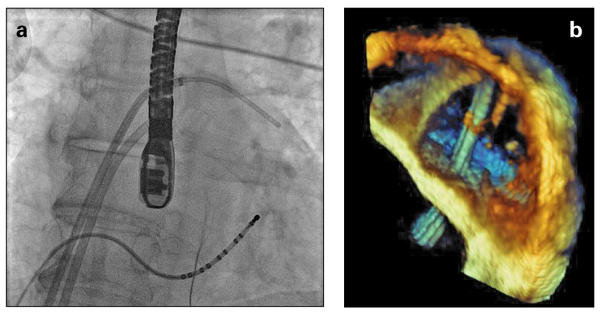

Abbildung 1a-b: Produkt: EchoNavigator Vertrieb: Philips Gängige Ansicht einer septischen Punktion (a) Röntgenaufnahme und (b) 3D-TEE-Bild liegen zusammenhanglos vor. © Philips |

Vertrieb: Philips Gängige Ansicht einer septischen Punktion (a) Röntgenaufnahme und (b) 3D-TEE-Bild liegen zusammenhanglos vor. © Philips |